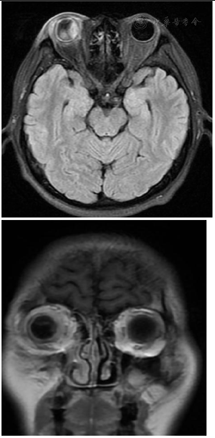

病例2,入院体格检查:体温36℃,脉搏92次/min,呼吸18次/min,血压96/79 mmHg,体质量75 kg。神志清楚,精神好。体格检查:普通视力检查:右手动/10 cm,左0.4眼压检查(非接触式眼压计);右Tn左11 mmHg裂隙灯检查:右眼:眼睑无水肿、充血、破溃、裂伤,结膜混合充血,角膜内皮可见大量菌栓附着,巩膜无黄染、结节,房闪(+++),虹膜:纹理清,无前粘,后粘,色泽正常,圆,居中,光敏,瞳孔药物性散大,晶状体密度增高,前囊可见渗出膜,玻璃体:积脓。间接眼底镜检查:视不清。裂隙灯检查:左眼:眼睑无水肿、充血、破溃、裂伤,结膜无明显充血,角膜透明,巩膜无黄染、结节,前房深度可,房闪(-),虹膜:纹理清,无前粘,后粘,色泽正常,瞳孔大小3 mm×3 mm,圆,居中,光敏,晶状体密度增高,玻璃体:混浊;间接眼底镜检查:小瞳下网膜未见明确出血及渗出。诊断:右眼EE。余心肺腹体格检查无特殊。实验室检查:乙肝、丙肝、HIV阴性;尿常规、甲功五项、糖化血红蛋白阴性、脑脊液正常、阴性。肿瘤标志物:血清铁蛋白1109 ng/ml;结缔组织疾病阴性;血常规:白细胞18.13×109/L↑,中性粒细胞占比0.848↑,血红蛋白111.00 g/L↓,血小板计数418.00×109/L↑;2022年8月1日门诊红细胞沉降率测定:58.00 mm/h↑;急诊炎症因子组合:C反应蛋白(干化) >90.00 mg/L↑,白细胞介素6 107.5 pg/ml↑,降钙素原全定量1.14 ng/ml↑。血培养、肝脓肿脓液培养:肺炎克雷伯菌(全敏感)。余心肺腹体格检查无特殊。头颅及腹部MRI:(1)脑MRI平扫及增强扫描未见明显异常;(2)右侧眼环增厚,右侧视网膜脱离,右眼玻璃体内异常信号,右侧泪腺及右侧眼眶周围软组织水肿,考虑炎性改变,请结合相关专科检查;(3)肝内多发异常信号,结合病史,考虑多发肝脓肿,肝门区及腹膜多发淋巴结,部分肿大;(4)胆囊炎;(5)肝周少量积液;(6)扫及双侧胸腔少量积液;扫及右肺内异常信号,建议结合胸部CT检查。腹部CTA提示:(1)肝内散在低密度灶,考虑脓肿可能,请结合临床;(2)胆囊炎;副脾;(3)腹膜后散在淋巴结;(4)右侧胸腔积液并部分肺不张,左侧胸膜不均匀性增厚;(5)腹部CTA示左肾双支肾动脉,第三肝门显影。超声造影:肝实质内多发混合性占位灶并其内多发分隔,结合超声造影考虑:肝脓肿并部分液化(图4、图5)。